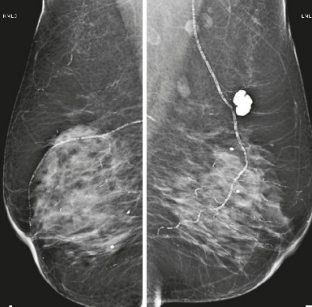

A mamografia abaixo é de uma paciente de 51 anos.

Observe a imagem acima e indique a classificação do BI-RADS.